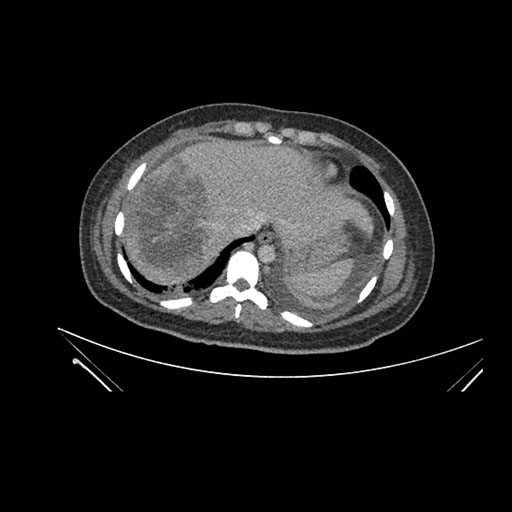

Axial Arterial

Axial Venous

Imaging analysis

Based on initial findings, which issue(s) would you be most concerned about?